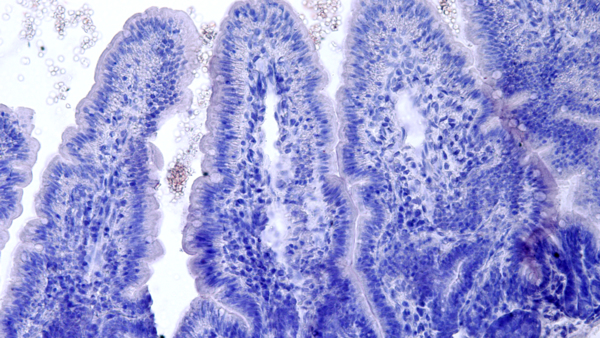

Bild: Andrea Puhar lab

Mekanism och inflammatorisk påverkan av extracellular ATP-signalering I tarmbakterier

Projektet syftar till att förstå hur extracellulär ATP-beroende signalering i kommensala och patogena tarmbakterier påverkar utvecklingen av tarminflammation.